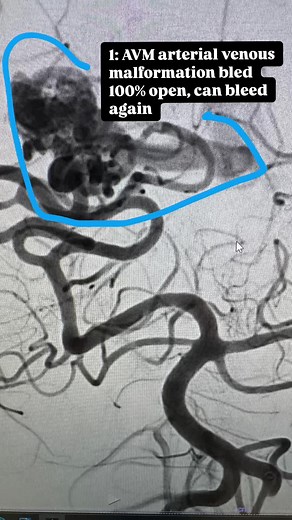

- Bavm

Brain - Arteriovenous Malformations

Malformation - Brain

Fistula - AVM